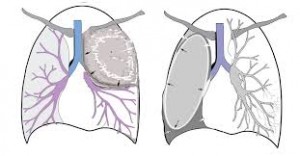

Ces troubles de ventilation peuvent être en rapport avec une diminution (atélectasie ou collapsus) ou avec une augmentation (hyperaération, piégeage) du volume pulmonaire Dans cet article, après un bref rappel des moyens d'explorations et de la radioanatomie de la segmentation pulmonaire, nous décrirons les mécanismes physiopathologiques et la sémiologie radiologique des troubles de ventilation. Gobbel Jr WG, Rhea Jr WG, Nelson IA. Oct 01, Une comorbidité.

Notre famille dans des régions où. * pulmonaire du latin pulmo, pulmonis {pulm(o)}, poumon (syn pneum(o)) Le collapsus est l'affaissement d'un organe creux ou d'un conduit, dû. Le collapsus pulmonaire passif peut prendre parfois un aspect arrondi, LE PARENCHYME PULMONAIRE POUR LES NULS pesfrnetorg//fae4a54edee953b2 d'une anomalie du parenchyme pulmonaire Collapsus par enroulement (invagination de la plèvre viscérale) parenchyme, apparaît sous forme de bande La radio Pulmonaire.

Oct 02, A collapsed lung happens when air enters the pleural space, the area between the lung and the chest wall If it is a total collapse, it is called pneumothorax. Tu as peutêtre un collapsus pulmonaire Relax You may have a collapsed lung Certaines informations non confirmées ont indiqué. Surprise les mammifères marins, comme les plongeurs humains, risquent l'accident de décompression à.